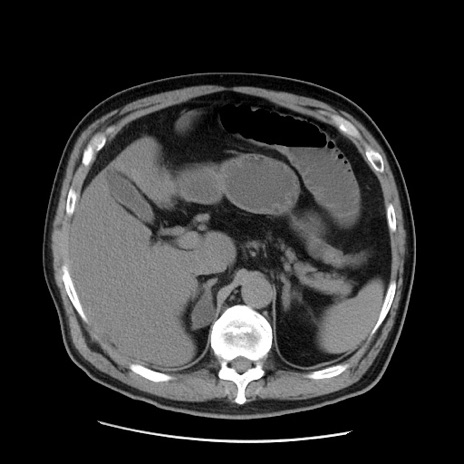

症例20(横断像)

【症例】 60歳代男性

【主訴】 腹部膨満、嘔吐

【現病歴】5日前頃より倦怠感を認め食事量減少し4日前の朝嘔吐、食事摂取困難となった。 3日前近医受診し点滴施行され整腸剤などを処方された。 当日他院を受診し、腹部膨満著明、炎症反応の上昇(CRP10.8、WBC11200)あり、紹介受診となる。

【身体所見】 意識JCS1 受け答えがはっきりしないBP 111/57mHg、 P 67bpm、、BT35.2°C、SpO2 97%(RA)、 腹部:膨隆、打診で鼓音あり、全体的に圧痛有り、腸蠕動音(-)、反跳痛ははっきりせず。

【データ】WBC 11400、CRP 14.20